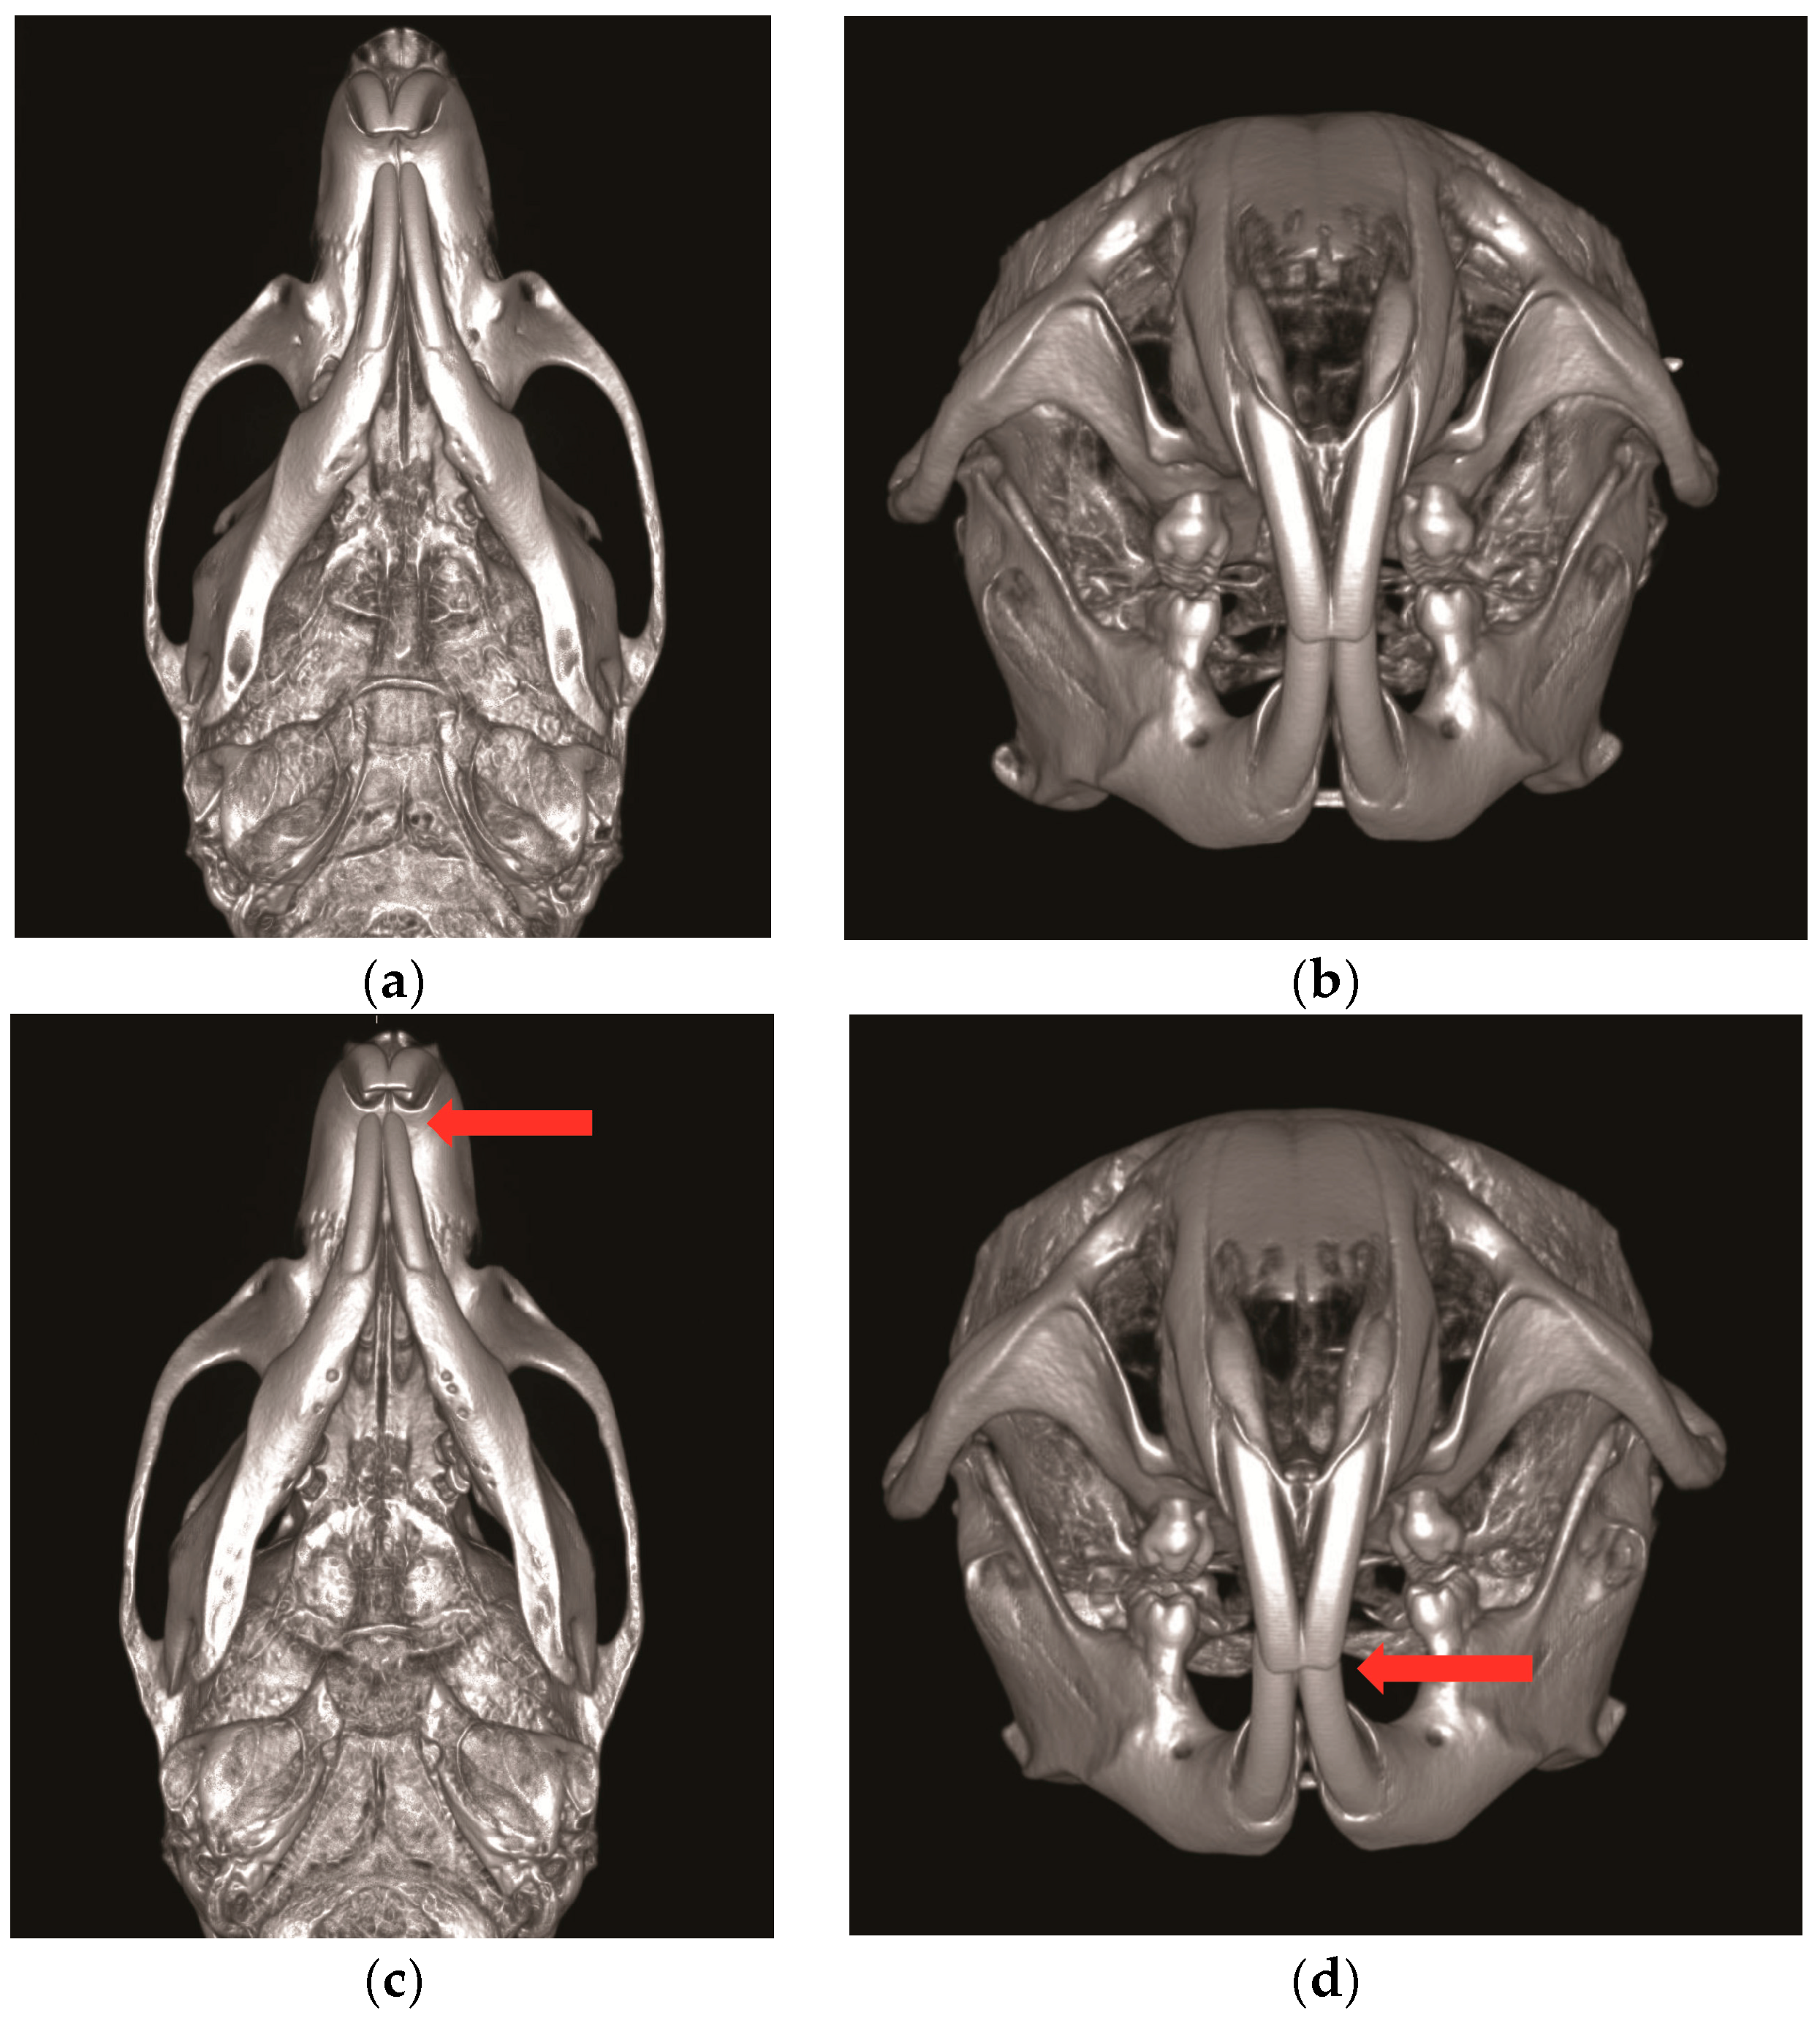

- Chen, Z.; Chen, Z.; Zhao, N.; Shen, G. An animal model for inducing deviation of the mandible. J. Oral Maxillofac. Surg. 2015, 73, 2207–2218. [Google Scholar] [CrossRef] [PubMed]

- Tsai, C.; Yang, L.; Chen, K.; Chiu, W. The influence of masticatory hypofunction on developing rat craniofacial structure. Int. J. Oral Maxillofac. Surg. 2010, 39, 593–598. [Google Scholar] [CrossRef] [PubMed]

- Matic, D.B.; Yazdani, A.; Wells, R.G.; Lee, T.Y.; Gan, B.S. The effects of masseter muscle paralysis on facial bone growth. J. Surg. Res. 2007, 139, 243–252. [Google Scholar] [CrossRef] [PubMed]